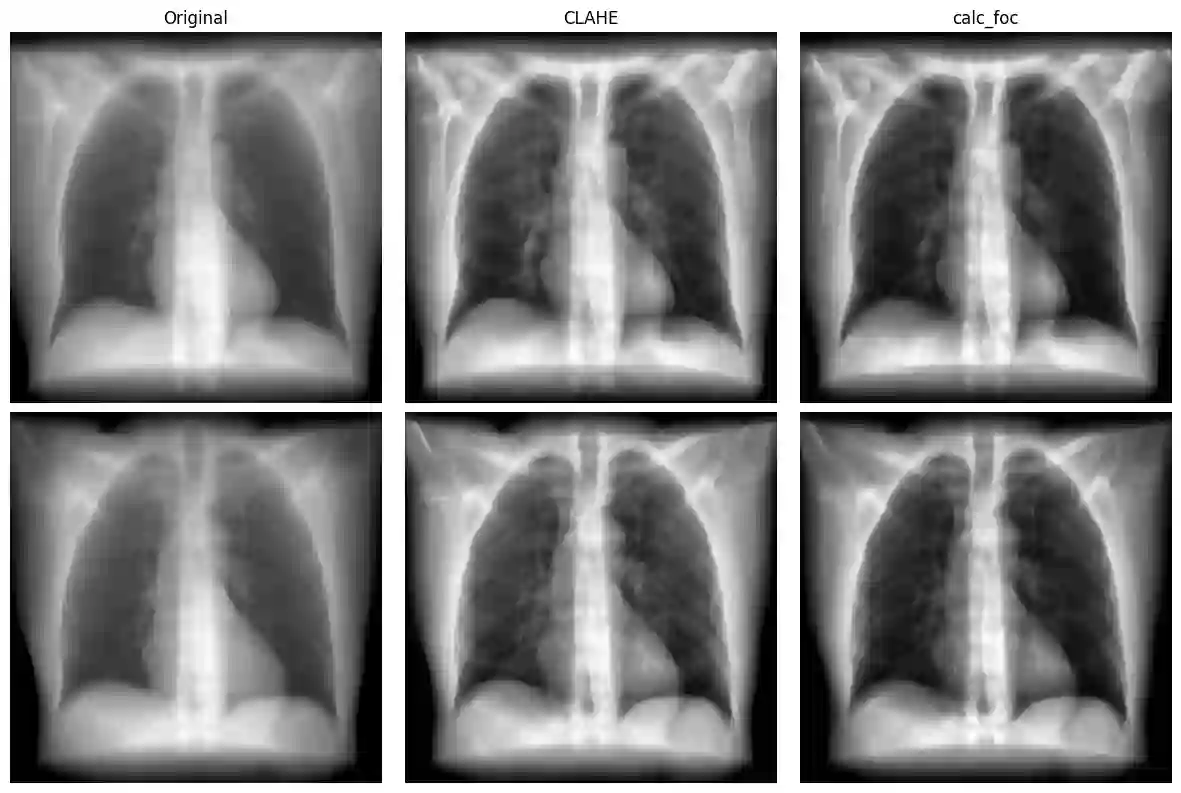

Coronary artery calcification (CAC) is a strong predictor of cardiovascular events, with CT-based Agatston scoring widely regarded as the clinical gold standard. However, CT is costly and impractical for large-scale screening, while chest X-rays (CXRs) are inexpensive but lack reliable ground truth labels, constraining deep learning development. Digitally reconstructed radiographs (DRRs) offer a scalable alternative by projecting CT volumes into CXR-like images while inheriting precise labels. In this work, we provide the first systematic evaluation of DRRs as a surrogate training domain for CAC detection. Using 667 CT scans from the COCA dataset, we generate synthetic DRRs and assess model capacity, super-resolution fidelity enhancement, preprocessing, and training strategies. Lightweight CNNs trained from scratch outperform large pretrained networks; pairing super-resolution with contrast enhancement yields significant gains; and curriculum learning stabilises training under weak supervision. Our best configuration achieves a mean AUC of 0.754, comparable to or exceeding prior CXR-based studies. These results establish DRRs as a scalable, label-rich foundation for CAC detection, while laying the foundation for future transfer learning and domain adaptation to real CXRs.